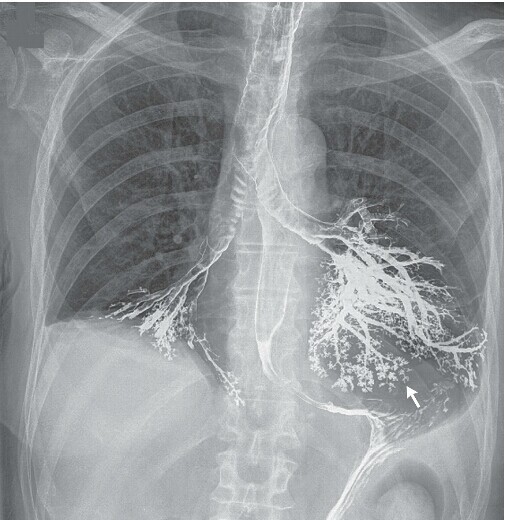

老年男性患者,因体重下降、吞咽困难就诊,并接受消化道钡造影检查,检查期间无呛咳等不适,检查结束后出行进行性恶化呼吸衰竭,进行气管插管后,入住 ICU进一步治疗,床旁胸部 X 线检查显示其左、右主支气管内均有钡剂存在,且基本显示出了支气管的轮廓,双肺下叶基底段支气管,左肺上、下叶的肺段支气管,均清晰显影;此外,钡剂也蔓延到了其较小的气道,并显示出树芽状(下图箭头处)的影像。支气管镜检证实患者的左、右肺下叶和舌叶均有钡剂存在,并吸出了大量钡剂。随即,患者出现休克,并出现心脏骤停,尽管经过了心肺复苏,液体复苏、应用正性肌力药和抗生素等紧急治疗,患者病情仍继续恶化;患者家属选择了保守的姑息治疗。患者于不久后去世。Mazen Albeldawi, M.D., and Rohit Makkar, M.D.N Engl J Med 2012; 366:1038;全文链接http://www.nejm.org/doi/full/10.1056/NEJMicm1108468。 消化道钡剂造影目前仍为临床常用检查方法,虽然钡剂误吸导致的呼吸衰竭并诱发死亡为罕见并发症,但不能忽视,需做好相关风险告知同时在出现对应情况时及时有效的处理